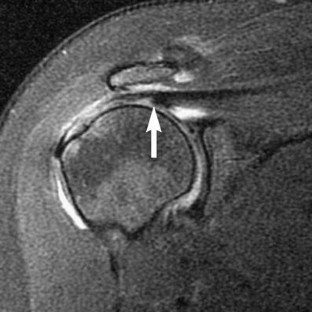

This study was reviewed and approved by our Institutional Review Board. The reports of 548 consecutive MR examinations of the shoulder were reviewed, looking for mention or description of delamination tears of the rotator cuff. The images of the identified cases were then reviewed by two radiologists to confirm the findings. Correlation with surgical and arthroscopic information was then performed. Delamination tears were defined as horizontal retraction of either the bursal or articular surface of the tendon, manifest as thickening of the torn retracted edge, and/or interstitial splitting of the tendon, manifest as fluid-like high signal intensity on fat-suppressed T2-weighted oblique coronal images.

Results

Fourteen cases of delamination tears were identified in 13 patients. Ten of the cases involved the supraspinatus tendon, all with articular surface involvement. Nine of these supraspinatus cases were isolated tears and one occurred as part of a full thickness tear. All 10 of these supraspinatus cases showed medial retraction of the articular surface of the tendon, with thickening of the retracted edge, and 5 of the 10 had a demonstrable horizontal cleft in the interstitium. Four cases involved the subscapularis tendon, with articular surface disruption in three and pure interstitial delamination in one. Medial subluxation of the tendon of the long head of the biceps was present in all four cases. No delamination tears occurred on the bursal surface. Only three of the 14 shoulders underwent surgical repair with one confirmation of supraspinatus delamination, one confirmation of a subscapularis tear that had become a full thickness tear 10 months after initial imaging and another interstitial subscapularis delamination that was not identified arthroscopically.

Delamination tears occur most often in the supraspinatus tendon, and in our series always involved the articular surface of the tendon. Only half of these tears have a visible cleavage plane in the interstitium, but this cleavage plane is not necessary for diagnosis if the torn edge is retracted.